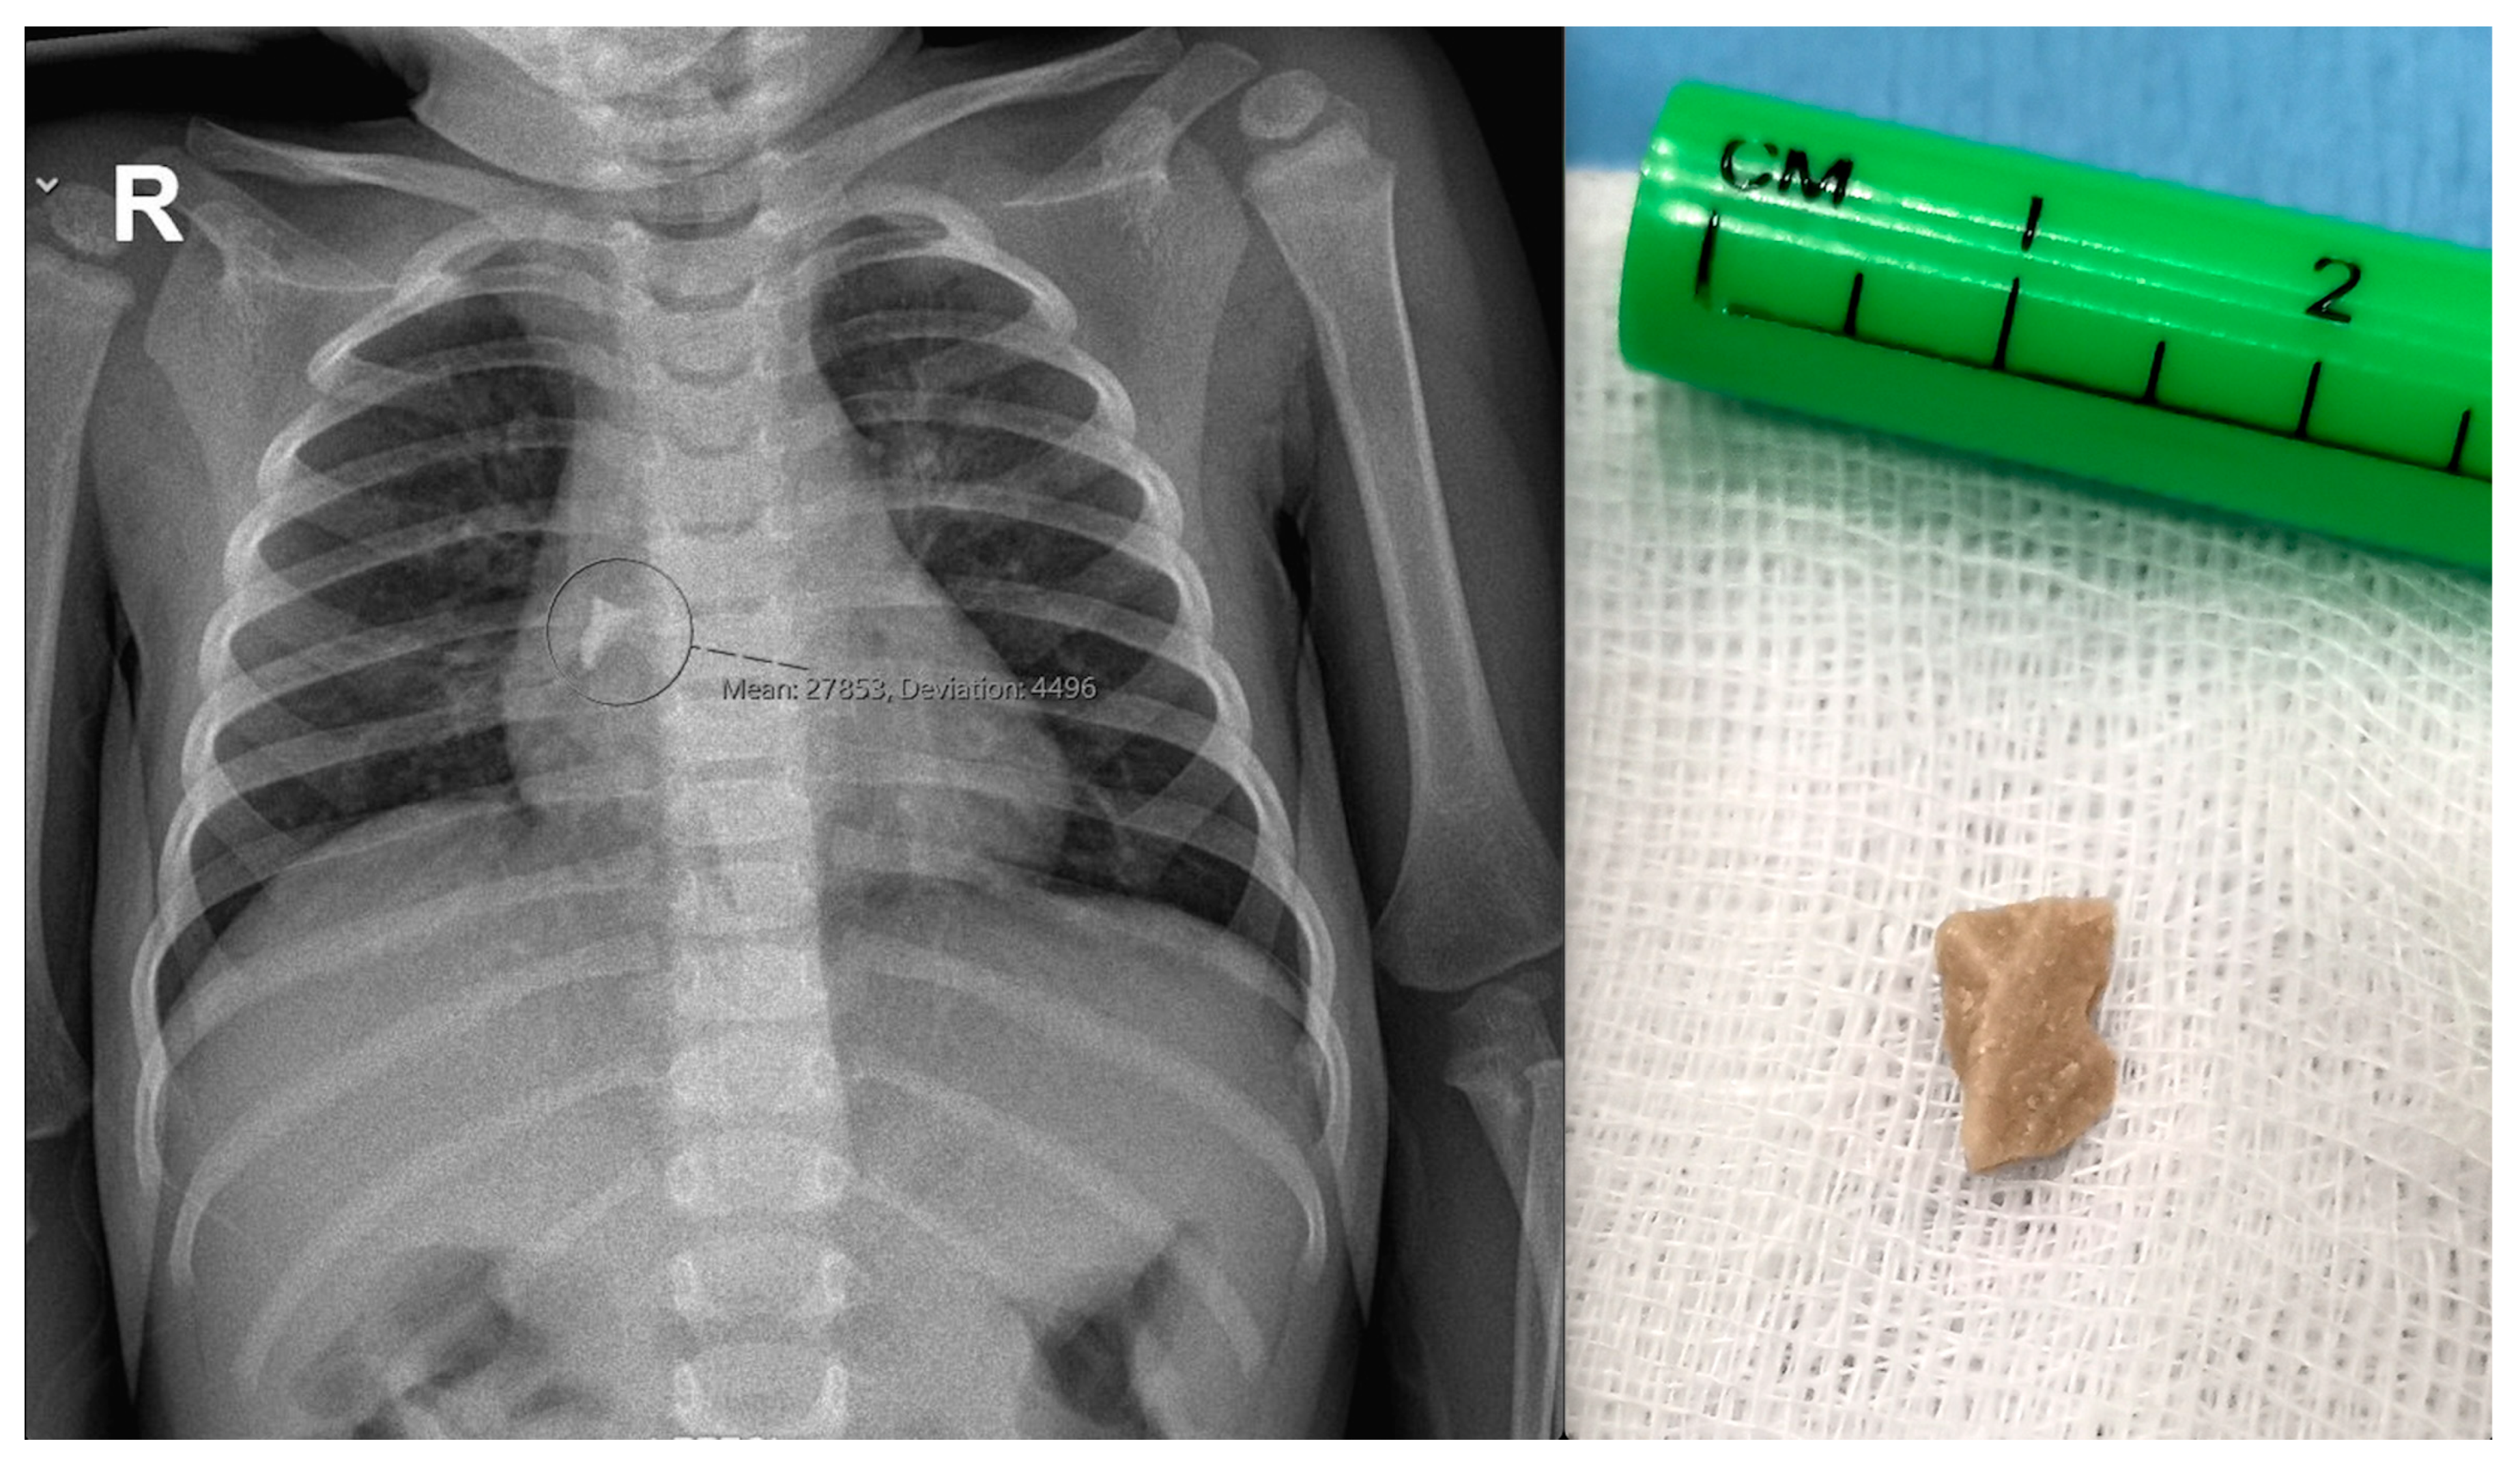

6. Tracheobronchial Foreign Bodies